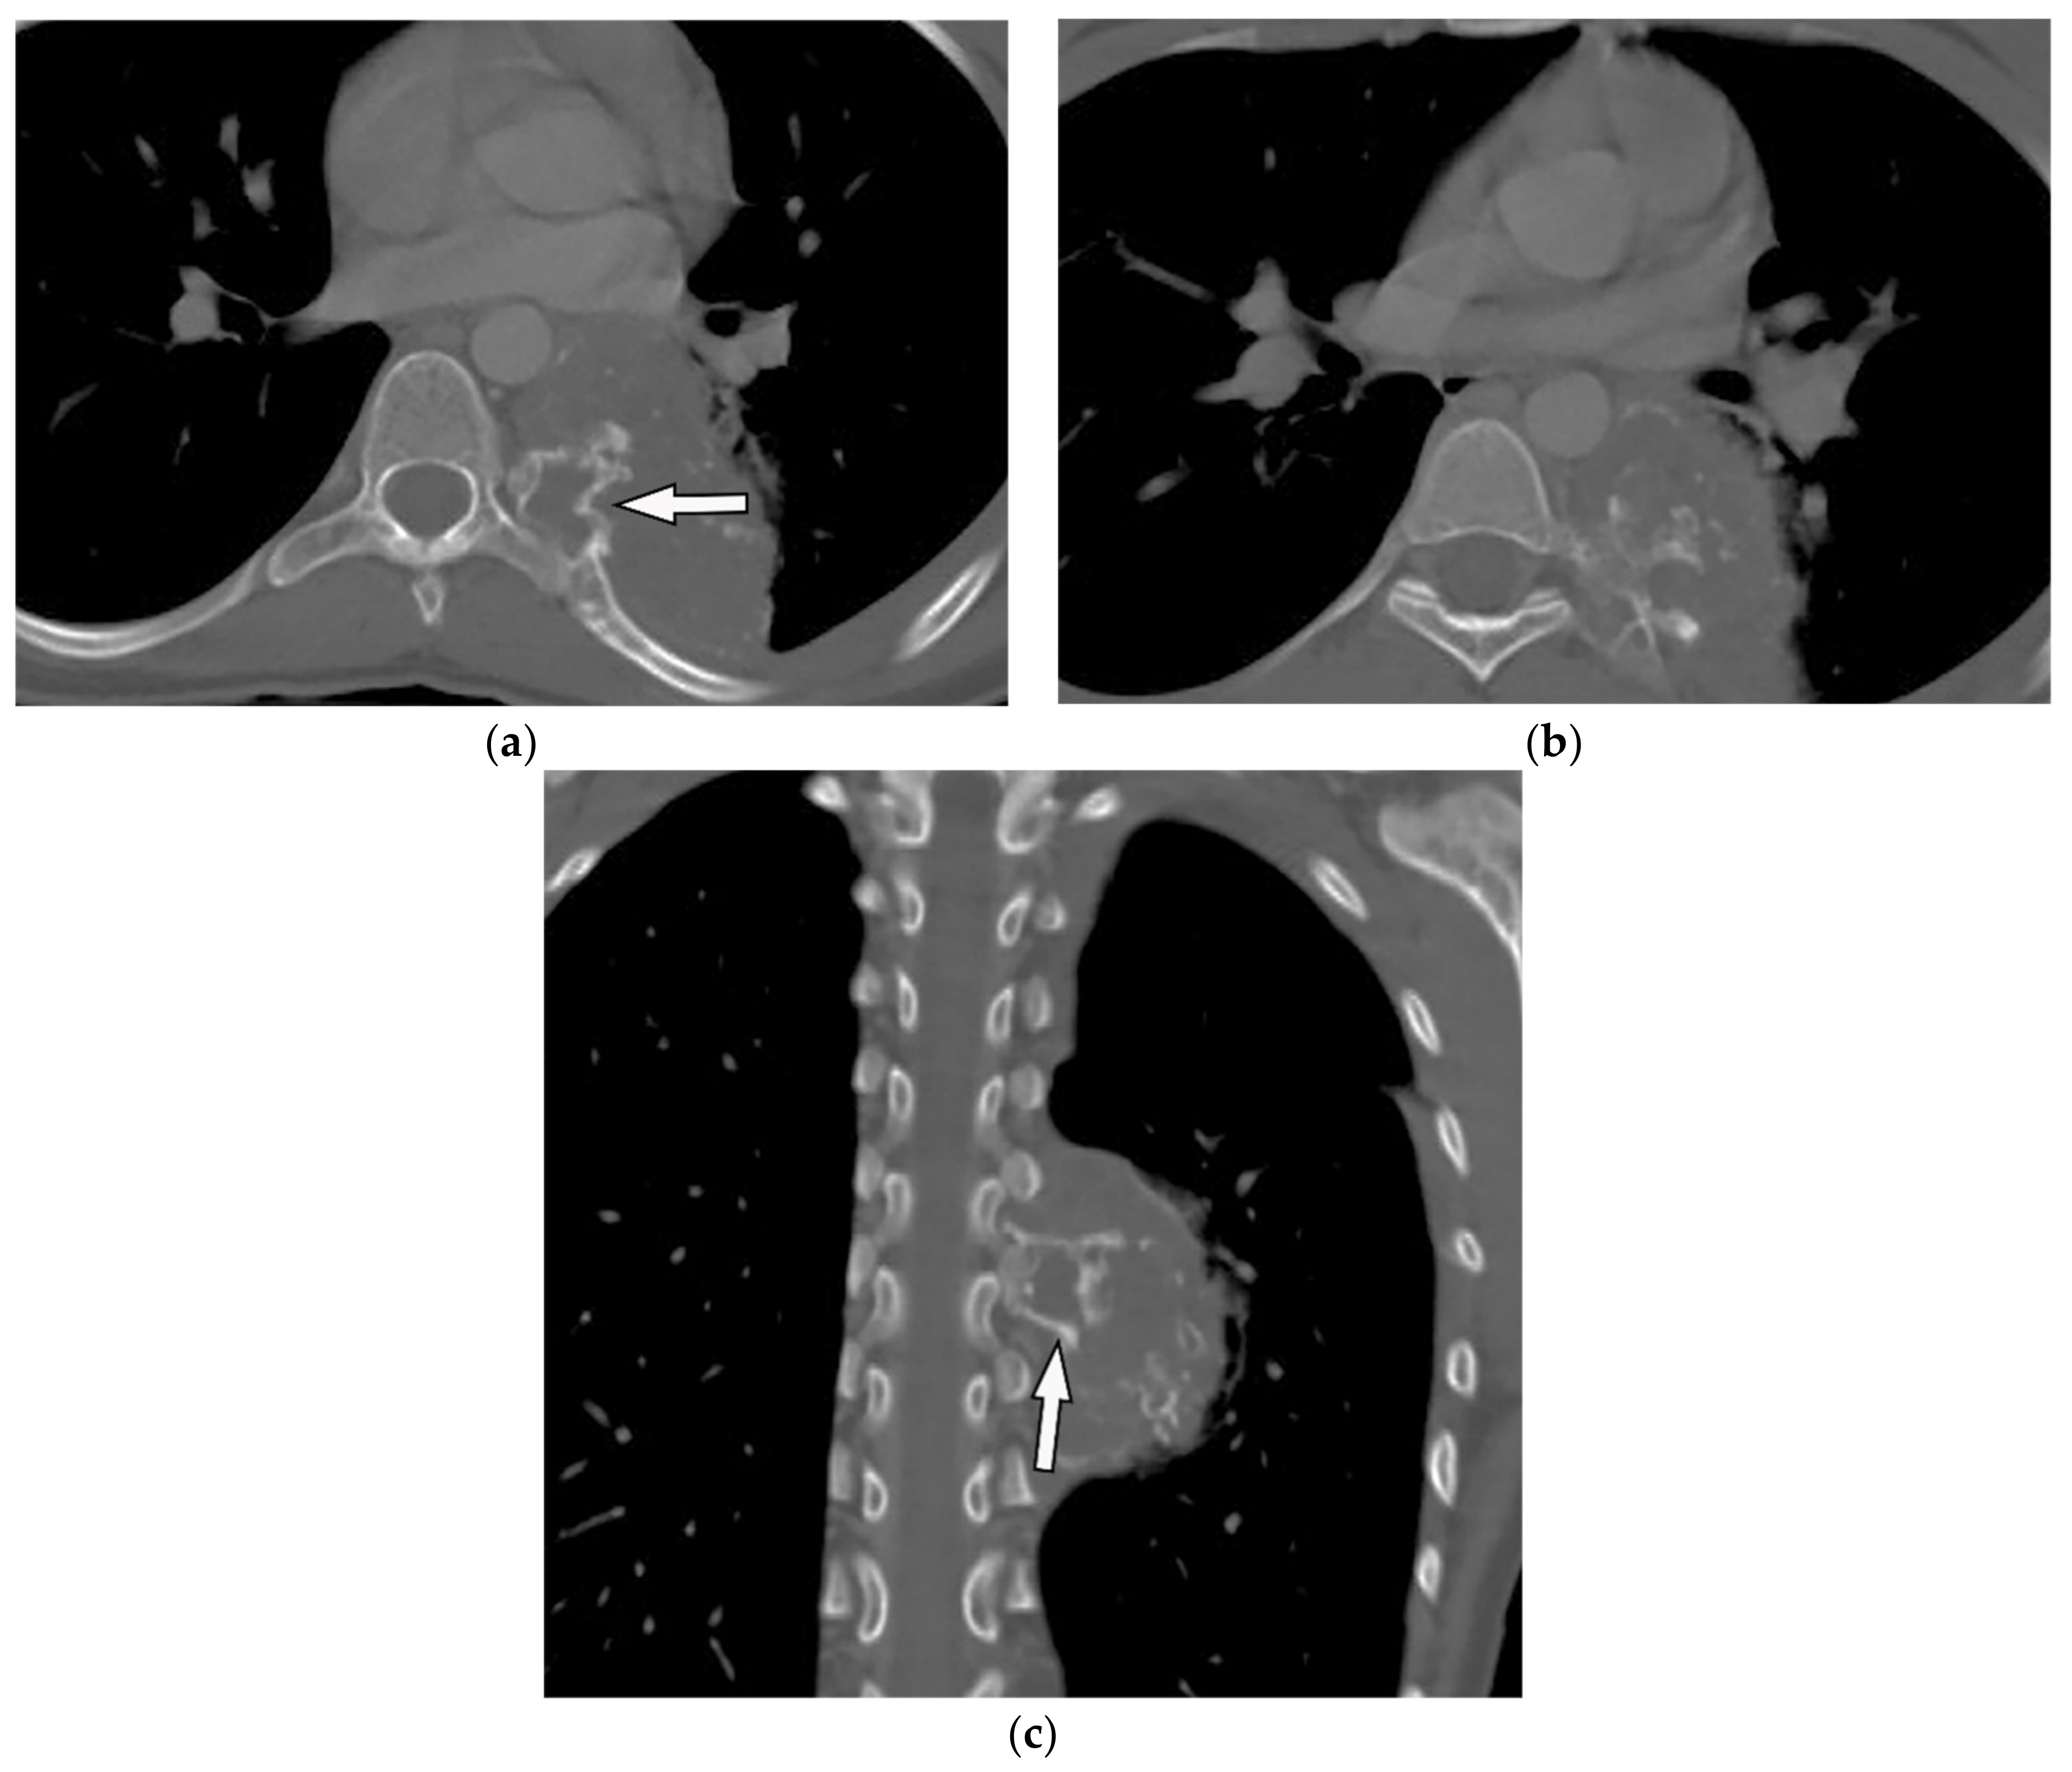

| Ewing sarcoma | Lytic bone destruction with ill-defined border, rare calcification, heterogenous paraspinal soft tissue with soft tissue larger than osseous component | T1W: iso to hyperintense to the muscle (high signal in hemorrhage) T2W: heterogeneous to hyperintense T1W FS + C: intense homogenous or heterogeneous enhancement |